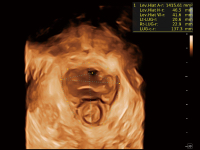

在传统血流的基础上优化扫查和算法策略,能够更好的抑制组织信息,提炼红细胞运动信息,得到更高帧频,高灵敏度和分辨率的血流信号,还原更真实的血流动力学。

通过光照模型,使二维血流显示出立体的效果,增加血流的敏感性、成束性,减少外溢。可以和其他不同的血流技术联合使用,融合不同技术的优势。轻松应对微小血管,增强血流的立体效果,提升视觉敏感性。